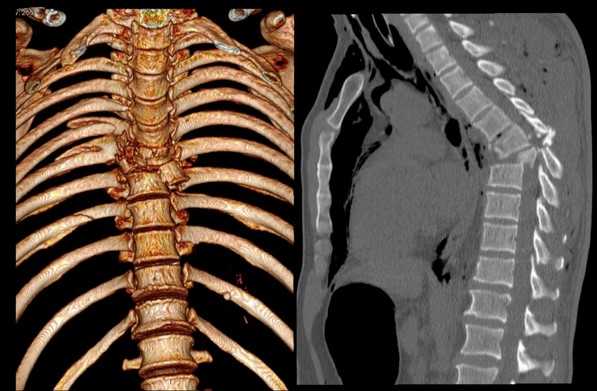

Перелом грудного отдела (трехмерная и сагиттальная проекции)

В результате компьютерной томографии получают серию послойных изображений рассматриваемой зоны. Монохромные фотографии обладают высоким разрешением. В отличие от рентгенографии на снимках отсутствуют дефекты и тени от расположенных рядом структур. Изменение плоскости при реконструкции изображений позволяет тщательно изучить анатомические образования. Преимуществом КТ является возможность создания 3D-модели позвоночника.